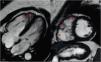

A 54-year-old female patient known to have hypothyroidism presented to the ambulatory care complaining of palpitations. The ECG recorded negative T waves in V1-V4. The two-dimensional echocardiogram showed a dilated RV. The 24-h Holter ECG highlighted frequent polymorphic ventricular extrasystoles and two episodes of non-sustained ventricular tachycardia. CMR revealed the following: dilated RV with RVEDV of 119 mL/m2, regional RV free wall akinesia with inflow, apex and outflow tract bulging (Figure 2). These sites are considered pathognomonic features of ARVC (the “triangle of dysplasia”).3 Axial black blood images showed irregularities between epicardial fat and anterior RV free wall, suggestive of fatty infiltration (Figure 2). Late gadolinium enhancement (LGE) was seen toward the RV apex and in the mid-epicardial layer of the apical left ventricular (LV) lateral wall (Figure 2). The diagnosis was ARVC with LV involvement.

(A) Cardiac magnetic resonance (CMR) horizontal long-axis CINE right ventricular (RV) anterior wall aneurysms; (B) CMR CINE RV outflow tract aneurysms; (C) axial black blood T1 RV free wall irregularities (fat infiltration); (D) RV apical and LV apical lateral wall late gadolinium enhancement.